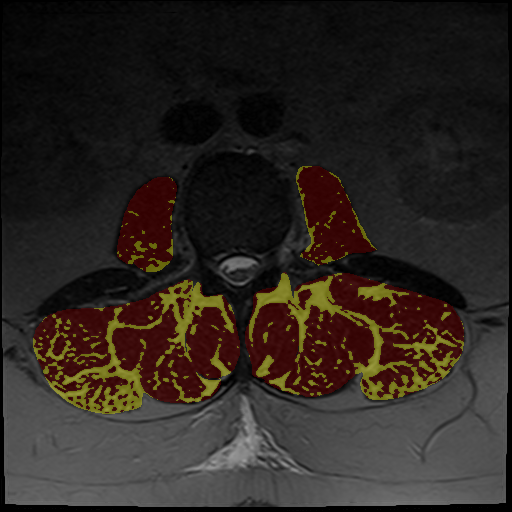

Automated muscle quantification

Extract muscle-specific metrics such as volumes or intramuscular fat percentage across multiple MRI contrasts and CT.